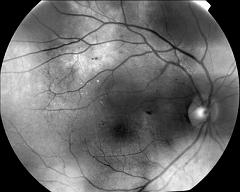

IM000001 |

IM000002 |

RADIAL LINE OD |

CROSS LINE OD |